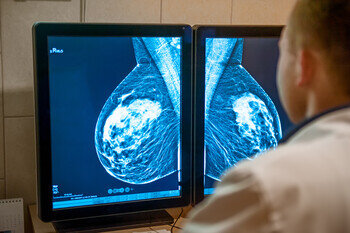

A few months on from a partial shutdown of what were considered non-urgent healthcare services – including cancer screening programmes – some drops and delays in cancer diagnoses have already been documented (Lancet Oncol 2020 June; 21:750-751). Now that several countries are once again tightening preventive measures in the face of rising COVID-19 case numbers, another potential reorganisation of healthcare is not far off and some are raising the alarm about indirect effects of the pandemic on global cancer mortality and morbidity.

“Only 10 percent of screening programmes have been able to continue in the past few months”, says Dr Richard Sullivan, King’s College London, UK, who co-led the development of the COVID-19 and Cancer Global Taskforce, among other things, to assess the impact of the pandemic on cancer outcomes. “Initial results of the Taskforce survey on global cancer screening show that about half of screening programmes have been only partially open and as many as 40 percent of the world’s screening activities are still suffering a complete shutdown.”

Social distancing measures, which are part of daily routine in healthcare since the COVID-19 outbreak, are another aspect that make screening units operate at lower capacity as Ginsburg reports from her own experience. The patients she sees carry mutations that give them an individual breast cancer risk of up to 60 percent for BRCA 1 and 2 genes or, in the case of Lynch syndrome, particularly predispose them to early-onset bowel or uterine cancers. “Our patients are proactive individuals: they have been diligent about maintaining their appointments and we have been fortunate to be able to absorb the backlog,” she says, sharing her concerns for other high-risk subjects who have not been screened yet. “About one in 300 Americans has a Lynch gene and one in 200 women in the US carries a BRCA genetic mutation, but the vast majority are not aware of it. In individuals with Lynch syndrome, for instance, the time sequence in which a benign polyp becomes an invasive cancer is greatly accelerated. That is why the fact that some of them missed or waited several months for a screening through standard prevention pathways is a real cause for concern.”

Even where screening services have been able to reopen, however, there has not been a return to normal care. “The problem is also bringing patients back, because it seems that people are not turning up as they should,” says Sullivan. “Have they just forgotten or are they still frightened to visit hospitals? In the UK, for example, there is still an incredible amount of bio-fear. Social science research is needed to understand these behavioural patterns towards screening in pandemics.” Based on the behavioural changes observed in past crises, however, Sullivan is pessimistic: “People simply stop going to their screenings because of financial instability or fatalistic attitudes that set in. This is a really insidious effect that hits the lowest socio-economic groups the hardest.”

How many people are missing their opportunity for early cancer diagnosis as a result? Some warn that disruptions in diagnostic services seem to be associated with a delayed presentation of asymptomatic patients missing the screening path as well as symptomatic patients, not timely referred to the appropriate care path. Sullivan has seen a worrying trend emerge in the UK: “Screening programmes have reopened to significant backlogs, but the diagnostic backlog for examinations like endoscopies and colonoscopies is much worse: currently 12 to 18 months and growing,” he reports. “We are already seeing people come in with advanced cancer, who had symptoms and should have been diagnosed in February.”

According to recent predictive modelling, 3,500 additional deaths at five years from diagnosis can be expected in England due to current delays in diagnostic processes across breast, lung, oesophageal and colorectal cancer (Lancet Oncol. 2020; 2020 Aug;21(8):1023-1034). Underlining that this estimate covers the impact for only four major tumour types in England and from diagnostic delays alone, Sullivan adds that it concerns relatively young individuals who might have had a chance of being cured if their disease had been detected earlier.  “COVID-19 compressed the mortality we would have had anticipated over the next year. The additional cancer deaths we can expect due to delays in healthcare provision, meanwhile, are going to weight with a significant proportion of years of life lost in addition to the deaths for COVID-19,” says Sullivan.